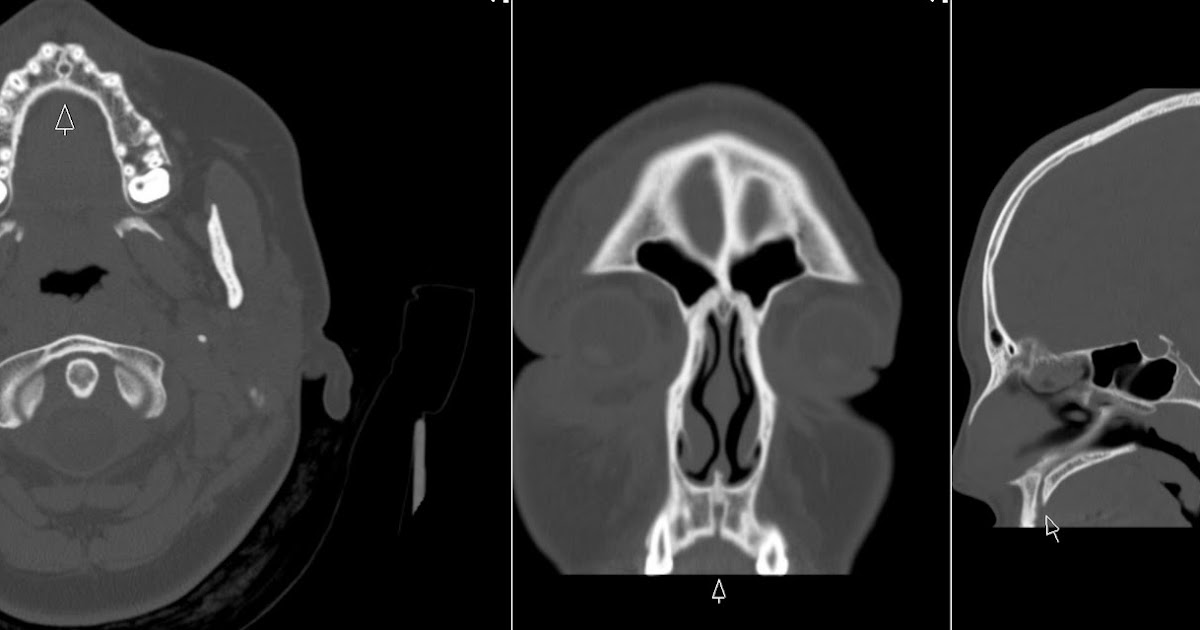

From www.mdpi.com

Applied Sciences Free FullText Aggressive Nasopalatine Cyst with Incisive Canal Cyst Symptoms It appears as either asymptomatic which is recognized on routine. They present as swelling of anterior hard palate, sometimes associated with pain and drainage. Incisive canal cysts, also known as nasopalatine duct cysts (npdcs), are developmental, nonneoplastic cysts arising from degeneration. It may appear as extrabony incisive papilla cyst or intrabony lesion. The incisive canal, also known as the nasopalatine. Incisive Canal Cyst Symptoms.